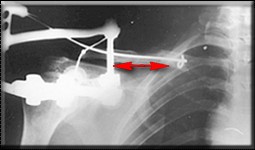

Re: Несросшийся перелом ключицы

Если заинтересует вариант фиксации трансплантата, представленный в приложении, с удовольствием поделимся опытом.